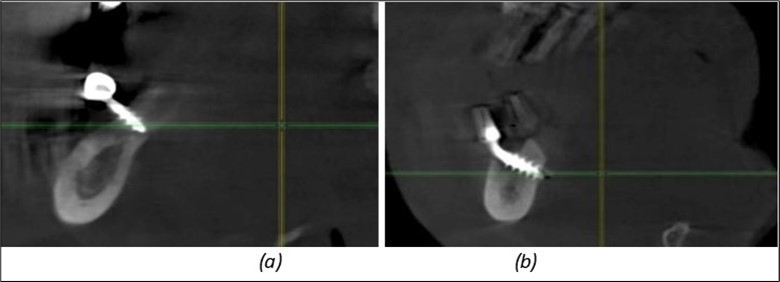

In the interforaminal area (Figure 3, Figure 13), 6 corticobasal implants are also placed. The increased number of implants is due to the poorly represented distal area that needs to be compensated.

Figure 12.Implants fixed distally in quadrant 4 with fixation at the level of the mylohyoid line: (a) The most distal implant fixed in unaffected bone from the previous restoration; (b) The implant fixed in the area where the two stage implant was removed.

Figure 13.Corticobasal BCS implants fixed between the vestibular and lingual cortices with support on the basal bone: (a) BCS fixed between the lateral cortices; (b) BCS implant with support on the basal cortex.